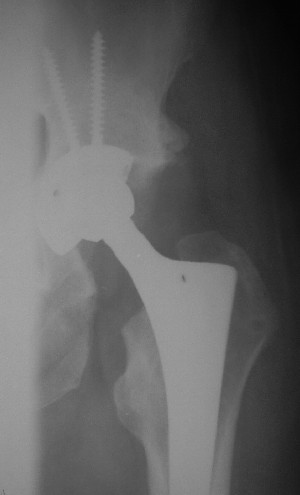

После протезирования прямой 5/04/04

После протезирования боковой 5/04/04

Больной 18 мая 2003 года в автоаварии получил перелом левой вертлужной впадины, вывих бедра. Госпитализирован в один из стационаров области.Вывих вправлен. В последствии бедро вывихивалось еще дважды. На консультацию был представлен снимок от 19.05.03г., больной переведен к нам 3.06.03г. Снимок при поступлении - перелом впадины, задне-верхний вывих бедра. 05.06.2003 г. выполнено открытое вправление вывиха левого бедра и остеосинтез стенки вертлужной впадины двумя винтами. Послеоперационный период без осложнений. Объем движений в левом тазобедренном суставе восстановился полностью. Выписан на амбулаторное лечение в удовлетворительном состоянии с рекомендациями 3 месяца ходить на костылях без нагрузки на оперированную конечность. На контрольных рентгенограммах левого тазобедренного сустава 13.10.2003 г. - признаки консолидации перелома; плотность, форма головки и состояние суставных поверхностей удовлетворительные. Разрешена дозированная осевая нагрузка, на конечность с использованием дополнительной опоры. 19.12.2003 г. больной обратился с жалобами на боли в левом тазобедренном суставе. На рентгенограммах левого тазобедренного сустава 19.12.2003 г., 20.02.04г. - асептичекий некроз головки бедра. 5.04.04г. - эндопротез. Сейчас ходит без трости, не хромает. Особенность эндопротезирования - при удалении винтов прослежена линия перелома заднего края впадины и предложено установить чашку несколько меньшего диаметра, чтобы она была покрыта несломанной частью.